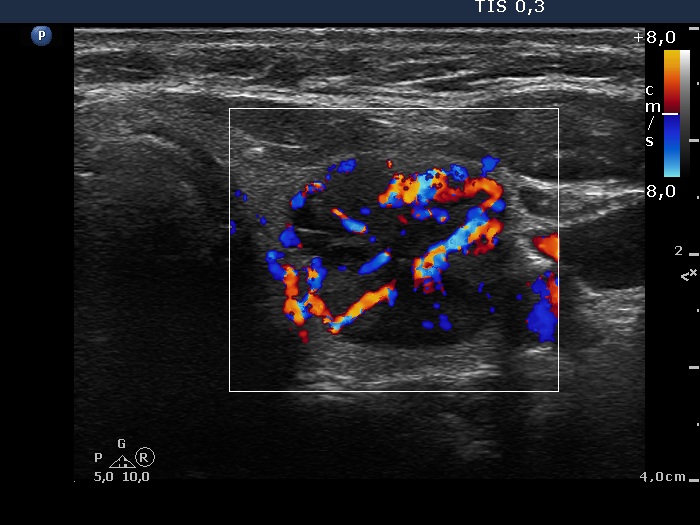

Study on 100 consecutive patients with thyroid nodule - case 052 (ultrasonographic picture 7)

Left lobe, transverse view, color Doppler mode. The nodule presents significantly increased, partly chaotic intranodular blood flow.